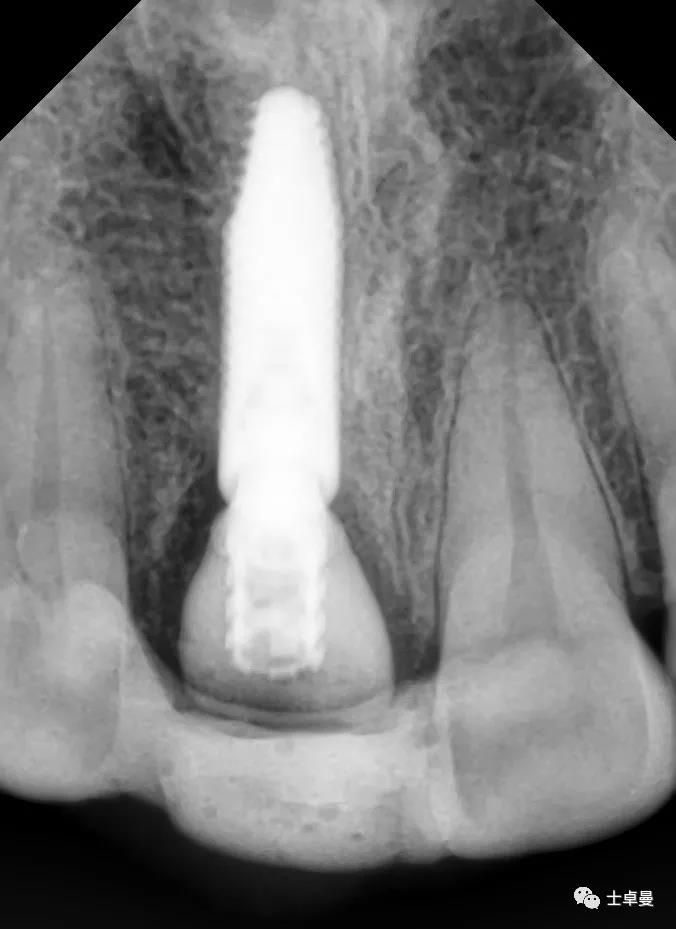

影像学检查,CBCT显示

· 11根管内充填致密,根尖未见明显阴影,根长约12mm;

· 唇侧牙槽骨完整,厚度约1.2mm;

· 根尖区剩余骨量约7mm。

术后即刻CT示,种植体植入位置理想

术后4个月复查,种植体周未见明显暗影

X线片示,临时修复体已就位

X线示,永久修复体已就位